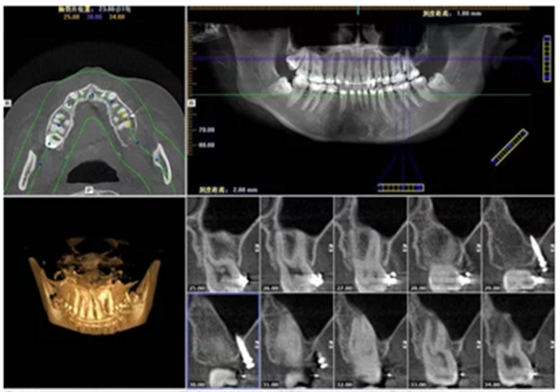

目前CBCT 廣泛應(yīng)用在口腔種植術(shù)前診斷與設(shè)計、口腔頜面部骨折和腫瘤、牙周疾病、顳下頜關(guān)節(jié)疾病、牙體牙髓疾病等領(lǐng)域,很大程度上取代了傳統(tǒng)的放射線檢查技術(shù)。CBCT 將掃描的頜骨影像數(shù)據(jù)導入相應(yīng)軟件中進行三維重建,并進行準確測量,從而可以全方位的進行手術(shù)模擬,進而合理設(shè)計種植體的型號尺寸,同時可以觀測種植體與上頜竇及下牙槽神經(jīng)管之間的距離,并且可以對頜骨骨量骨質(zhì)進行評估,以及模擬未來修復(fù)體與鄰牙對頜牙的位置關(guān)系等。

接下來,應(yīng)用口腔種植計算機設(shè)計軟件進行三維計算機輔助手術(shù)規(guī)劃,利用這些軟件仿真手術(shù)模擬放置種植體,檢查植入方向,未來義齒修復(fù)體的修復(fù)空間以及牙鄰牙的關(guān)系。將這些信息參數(shù)轉(zhuǎn)化STL文件格式,通過數(shù)控機床或用快速成型方法加工,最終完成數(shù)字化導板的制作;數(shù)字化外科導板作為信息載體,將種植思路通過導板轉(zhuǎn)移到了手術(shù)過程中。